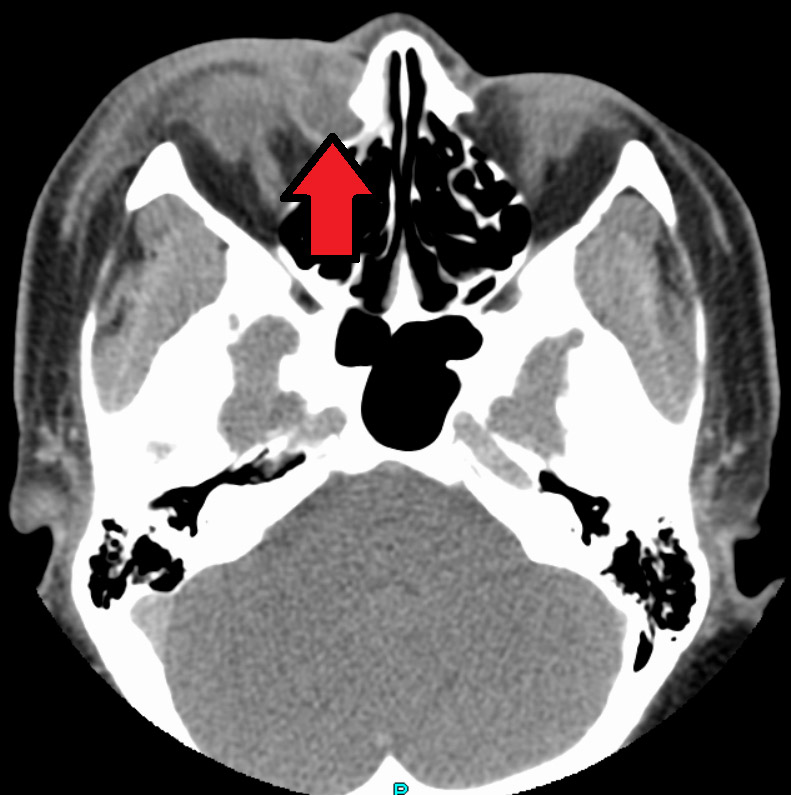

Dacryocystitis is an infection of the tear sac that lies between the inner corner of the eyelids and the nose. It usually results from blockage of the duct that carries tears from the tear sac to the nose.

The blocked duct harbours bacteria and becomes infected. Dacryocystitis may be acute (sudden onset) or chronic (frequently recurs). It may be related to a malformation of the tear duct, injury, eye infection, or trauma.

During the examination, the eye care practitioner will determine the extent of the blockage. Cultures may be taken of the discharge to identify the type of infection. The eye care practitioner will also determine whether the infection has affected the eye.